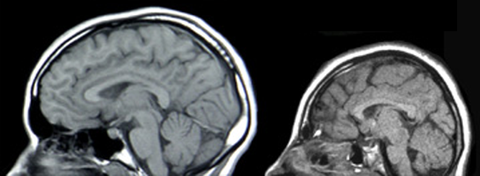

LISENCEFALIA: Es un trastorno poco común de la formación del cerebro caracterizado por microcefalia y agiria (ausencia de las circunvoluciones normales del cerebro). Es causada por una migración neuronal defectuosa, de modo que las células nerviosas se desplazan desde el lugar de origen a su localización permanente. Puede ser debido a infecciones virales, a la escasez de riego sanguíneo al cerebro del feto o a un trastorno genético. |

Image:

Lissencephaly (image/jpg)